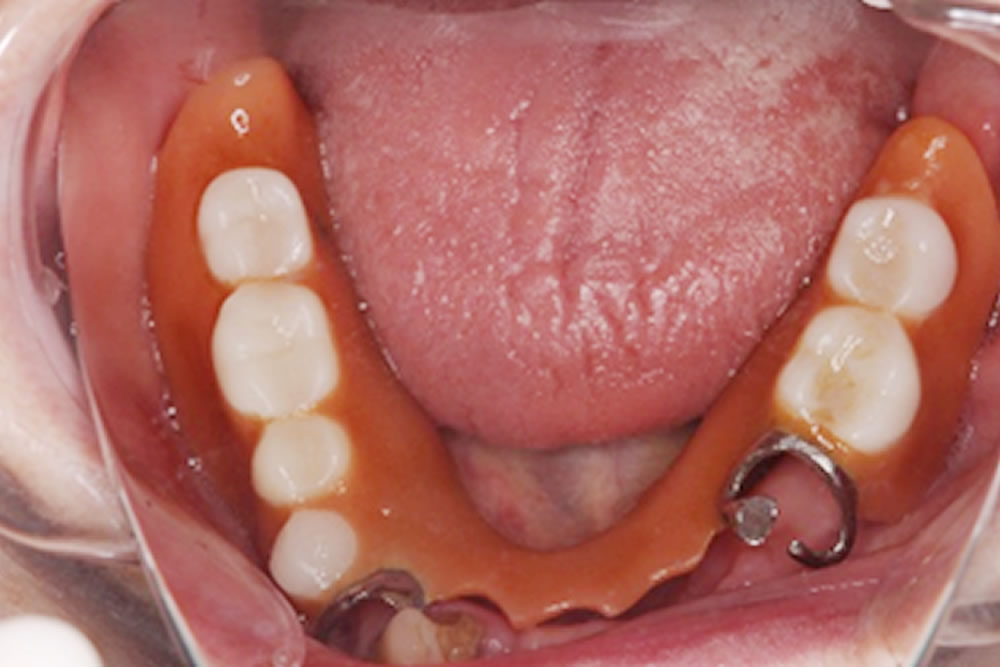

ご希望は、「昔作った入れ歯が噛みづらく、安定が悪くすぐに外れてしまう。見た目も悪いので作り直して欲しい」という内容でした。

入れ歯を作った後に抜歯をしているため、バネがかかる歯がなく入れ歯を維持する歯がない。残ったご自身の歯の本数も少なく入れ歯を支えきれない可能性がある上、入れ歯のバネをかけるのは歯の形態や状態に難がある。

先の歯周病検査の結果で、残った歯が入れ歯を支えるのに十分な強度があるかを調べ、強度は十分ではあるが単独だと長期的な安定は難しい思われるところは、残っている歯を連結することで安定を図りました。